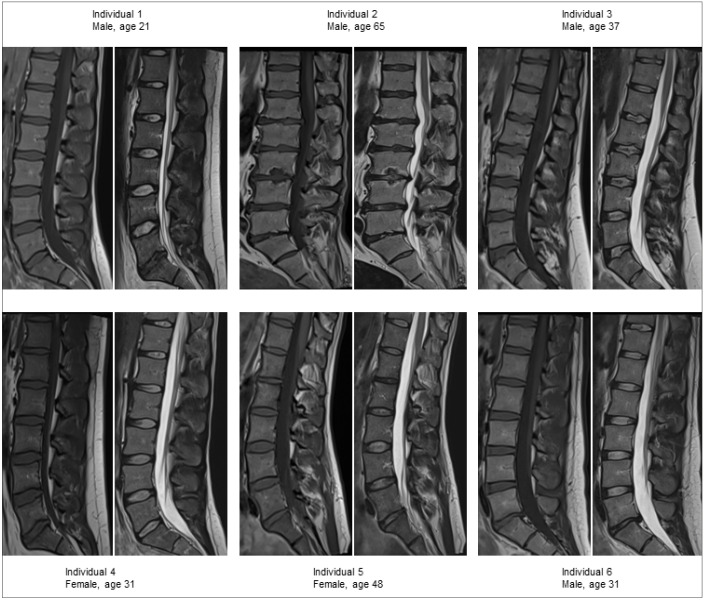

PURPOSE The increasing interest of endplate and Modic changes as potential pain generators in low back pain (LBP), along with advancement of functional quantitative magnetic resonance imaging (MRI) techniques, makes it important to characterize the vertebral dynamic behavior in detail. This study aims to perform characterization of the dynamic behavior of the vertebral bodies (VB) by investigating the VB diurnal variation in T2-relaxation time in a cross-sectional asymptomatic group of individuals. METHODS T2-mapping of 30 VBs (L1-L5) in six healthy volunteers (mean age, 40 years; range, 29-65 years) was performed with a 1.5 Tesla MRI at three time points over the day (7 am, 12 am, 5 pm). Volumetric regions of interest were segmented manually to determine VB T2-relaxation time, which was compared between the three time points. RESULTS On a group level only small and not significant diurnal VB variation was detected (all P >.10), with median T2 (ms) (quartiles; Q1, Q3) at the three time points 88.7 (84.1, 99.1), 87.3 (85.0, 96.1) and 87.8 (84.4, 99.2). However, in some VBs up to 7% increase respectively 9% decrease in T2-relaxation time was found during the day. Further, there was a relatively large variation between the individuals in absolute VB T2-relaxation times (range 73.2-108.3 ms), but small differences between the VBs within an individual. CONCLUSION This first T2-mapping study of the VB signal dynamics, in repeated investigations during one day, display variation in T2-relaxation time in specific individual VBs but were negligible on a group level. The result may be of importance when evaluating patients with spinal pathologies and suggest further examinations of dynamic changes not only of the disc but also vertebrae.

Abstract Image